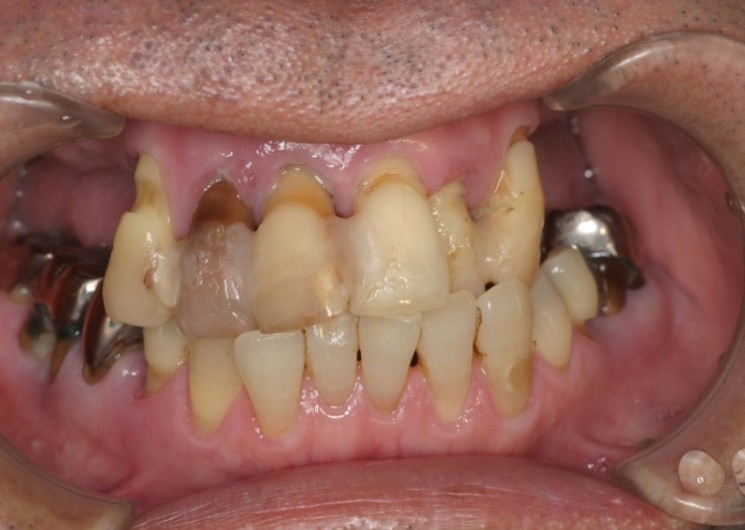

重度の歯周病により、他院で「総入れ歯にするしかない」と診断された40代の男性のケースです。

「まだ若いのに、会話中に外れるかもしれない恐怖と一生付き合うのか」患者様はそんな深い絶望を抱えて当院に来院されました。

治療前(口腔内写真)